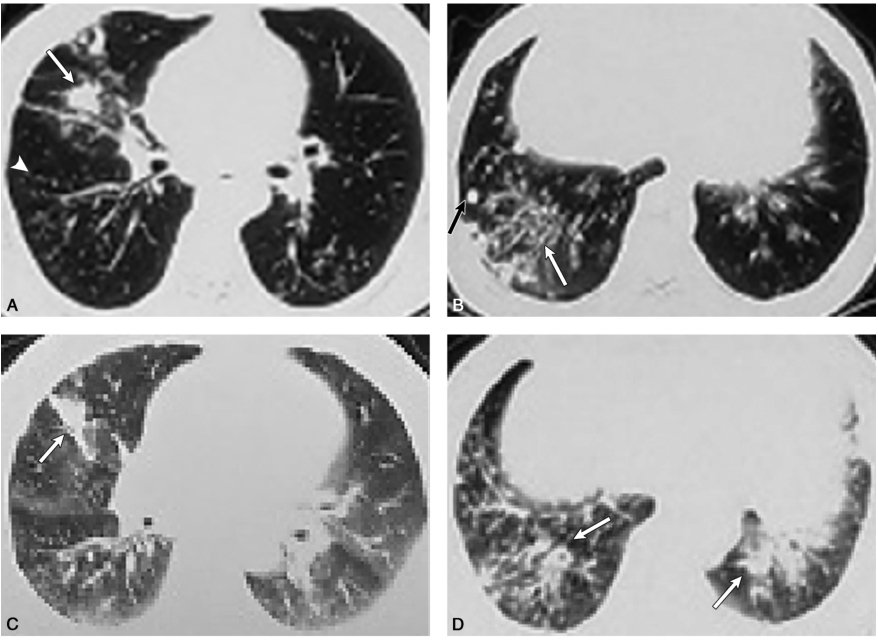

患者男性,60岁,私企老板。因“咳嗽、咳痰、气急半年余”入院。患者于2017年12月初开始出现咳嗽、咳痰,咳白色黏液痰,时有少许痰中带血丝,伴活动后气急、发热,体温在37~38℃,口服抗生素(具体不详)治疗后无好转。2017年12月16日于当地医院查胸部CT(图1A、B)示:“右肺中叶占位,两肺下叶结节,右肺中下叶及左肺下叶支气管扩张伴感染”。后在当地市中医院诊治,予抗感染、祛痰等治疗一周后体温正常,咯血止,但仍有咳嗽、咳痰。2017年12月24日再次于当地医院住院治疗,查胸部增强CT(图1C、D)报告“两肺弥漫性病变,较前片对比进展”。后转至上海某肿瘤医院,2018年1月3日行PET/CT示“右肺中叶及两肺下叶多发斑片致密影,结节影,条索影,FDG代谢略高”。予以“头孢类+左氧氟沙星”规律抗感染治疗4周,于2018年2月2日复查胸部CT提示双肺病灶无吸收。继续给予“哌拉西林/舒巴坦+阿奇霉素”抗感染治疗2周,仍有咳嗽、咳痰,且活动后气急明显。于2018年2月19日复查CT(图1E、F)报告“两肺炎症伴结节,两侧胸膜增厚,右肺中叶病灶较前有所吸收,双下肺病灶无吸收”。为进一步诊治,于2018年3月2日入我科。

图1外院不同时间点胸部CT扫描提示:双肺弥漫性细小结节影(白箭头),斑片影、实变影呈一定的游走性(白箭),并牵拉性支气管扩张和管壁增厚(白箭),近胸膜下多发实性结节影(黑箭)外院胸部CT平扫时间:2017-12-16(A、B);2017-12-24(C、D);2018-02-19(E、F)